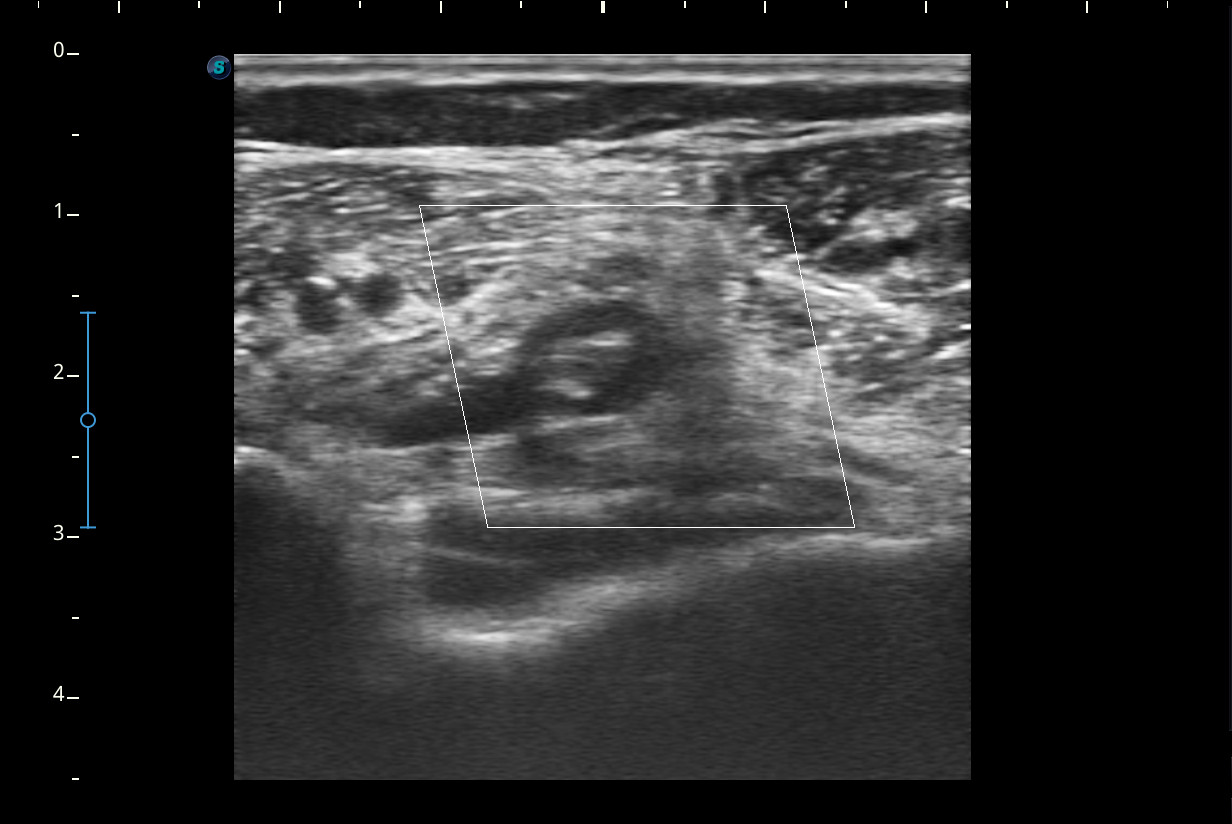

A nivel del hueco poplíteo se visualiza presencia de trombosis de la vena poplítea, no así en localizaciones proximales.Otras pruebas complementarias realizadas (si existen)